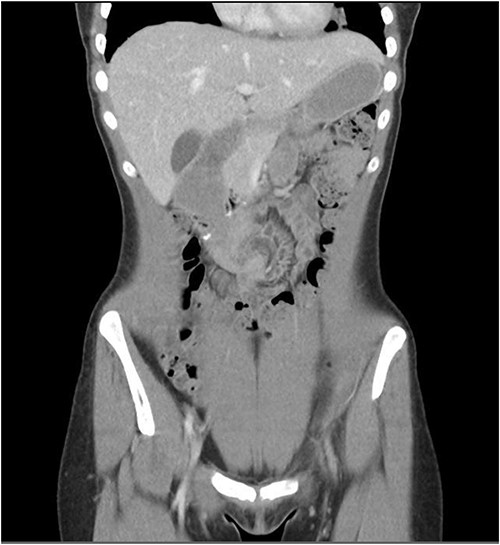

A duodenojejunostomy involves creating an anastomosis between the duodenum and the jejunum [4]. A review of what literature is available on duodenojejunostomy for SMA syndrome reports that most surgeon’s anastomosis the jejunum 20–30 cm from the DJ flexure [5]. Internal hernias are a very rare complication of a duodenojejunostomy and there is no literature on this phenomenon. This patient’s anastomosis occurred at 60 cm from the DJ flexure, which may have created a bigger defect and therefore made this patient more prone to an internal hernia.

The take away message from this case it to ensure that the anastomosis point of the jejunum is a short enough distance from the DJ flexure that a defect, through which small bowel can fall, is not created and therefore lead to an internal hernia.